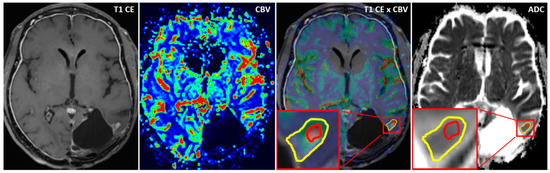

Using the MCEval ROI (region of interest) tool of the mean curve plug-in of MR neurology, two ROIs were manually placed by a neuroradiologist (authors F.E. and M.A.S.) on the image slice depicting the largest lesion diameter in the co-registered MPRAGE x DSC map: a selective ROI in the contrast-enhancing lesion area with the highest CBV value excluding vessels and nontumorous tissue, and an unselective ROI contouring the whole contrast enhancing lesion including necrotic or cystic areas. Then, both ROIs were copied onto the corresponding ADC map. A third ROI was placed in the co-registered CBV perfusion and ADC maps in the contralateral healthy white matter excluding vessels, cerebrospinal fluid, and bone. Figure 1 and Figure 2 show exemplary measurements in a patient with recurrent GBM and a patient with TRC. Image post-processing and manual ROI placement took approximately 4 min.

Figure 1. Exemplary cerebral blood volume and apparent diffusion coefficient measurements in a patient with recurrent glioblastoma. Exemplary apparent diffusion coefficient (ADC) measurement of a selective region of interest (ROI) (red) in the contrast-enhanced area with the highest cerebral blood volume (CBV) and an unselective ROI (yellow) comprising the whole contrast-enhancing lesion in a patient with recurrent glioblastoma (GBM). After placing the ROIs carefully in the fused CBV x contrast-enhanced T1 sequence map, ROIs are copied to the exact same position in the corresponding ADC map.